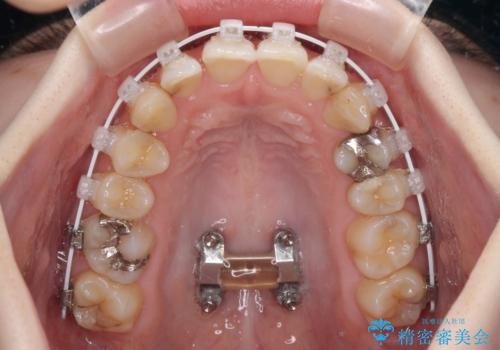

短期間での治療 急速拡大装置を併用したワイヤー装置による矯正治療

- 急速拡大装置・審美装置

上顎骨の横幅が狭く、上下ともに内側に倒れ込んだ混み合った歯列となっていました。

急速拡大装置により上顎骨を側方に拡大し、ワイヤー装置により歯列を整えることとしました。